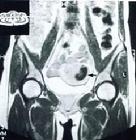

B超所見:實質性卵巢腫物約70%為惡性;囊性與實性混合型腫瘤也多屬惡性。B超檢查若發現腫瘤壁厚(實性反射厚度超過2厘米)應高度可疑惡性。CT檢查、核磁共振成像(MRI)檢查可輔助診斷。